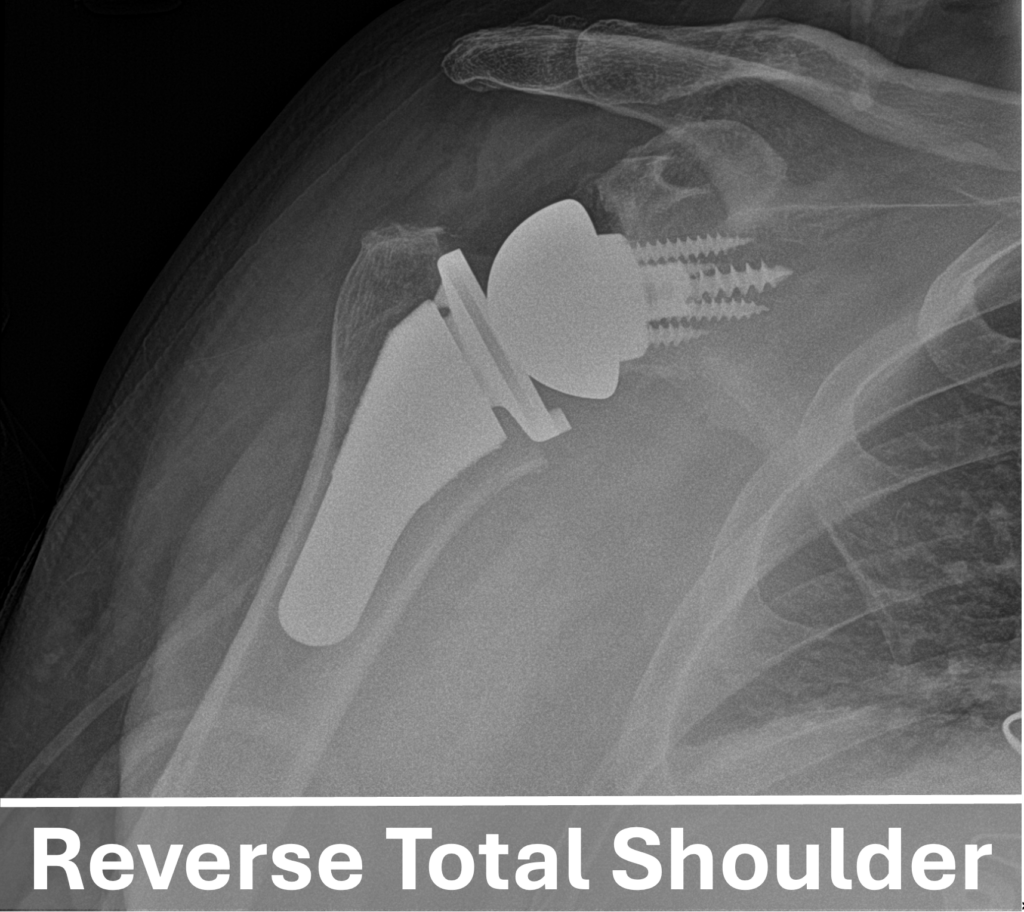

Since its introduction in 1987 (in Europe) and 2004 (in the United States), the reverse total shoulder arthroplasty has become a reliable procedure for managing various shoulder conditions. This modern surgical innovation is particularly beneficial for patients with conditions that traditional shoulder replacements cannot address, such as Irreparable rotator cuff tears, fractures, and chronic dislocations.

In this procedure, the positions of the shoulder’s ball and socket are structurally “reversed”. Therefore, the metal ball is attached to the scapula (where the socket normally is) and the artificial socket is affixed to the upper arm bone / humerus (where the ball normally is).

This unique design offers greater stability and allows the stronger deltoid muscles to move the arm, making it particularly beneficial for patients who do not have a functional rotator cuff. It is also helpful for those with significant bone deformities, complex shoulder fractures, or previous unsuccessful shoulder surgeries. Due to these advantages, the reverse total shoulder replacement has become the most common type of shoulder replacement surgery performed in the United States.